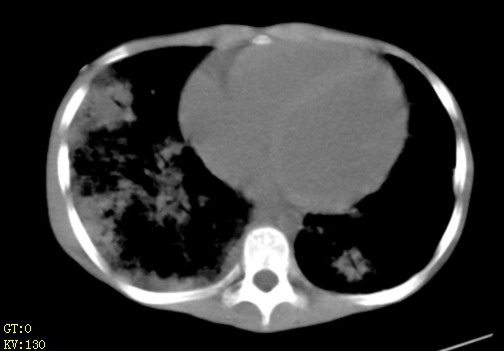

女,12岁,气促、咳嗽2天,3个月前查胸片示:两肺感染,急诊入院查ct,血常规等未检查。

左肺上叶改变考虑继发性肺结核,余双肺重症肺炎不排除h1n1。双侧胸腔少量积液。

1、左心房、左心室增大,考虑左心衰, 2、肺水肿合并感染 3、双侧胸腔积液

双肺中下野不规则片絮状阴影,中外带明显,双侧胸腔少量积液,心影增大,心腔密度减低,隆突下及左侧气管旁见钙化淋巴结影,考虑双肺感染、心衰;建议结合临床除外h1n1并急性心衰,先心不能排除。

两肺多发片絮状模糊影,以下肺外带居多,内见支气管气像,纵膈窗未减影,两侧胸腔积液,心影增大,结合心超,支持重症肺炎,非常时期,甲型h1n1流感不排除。